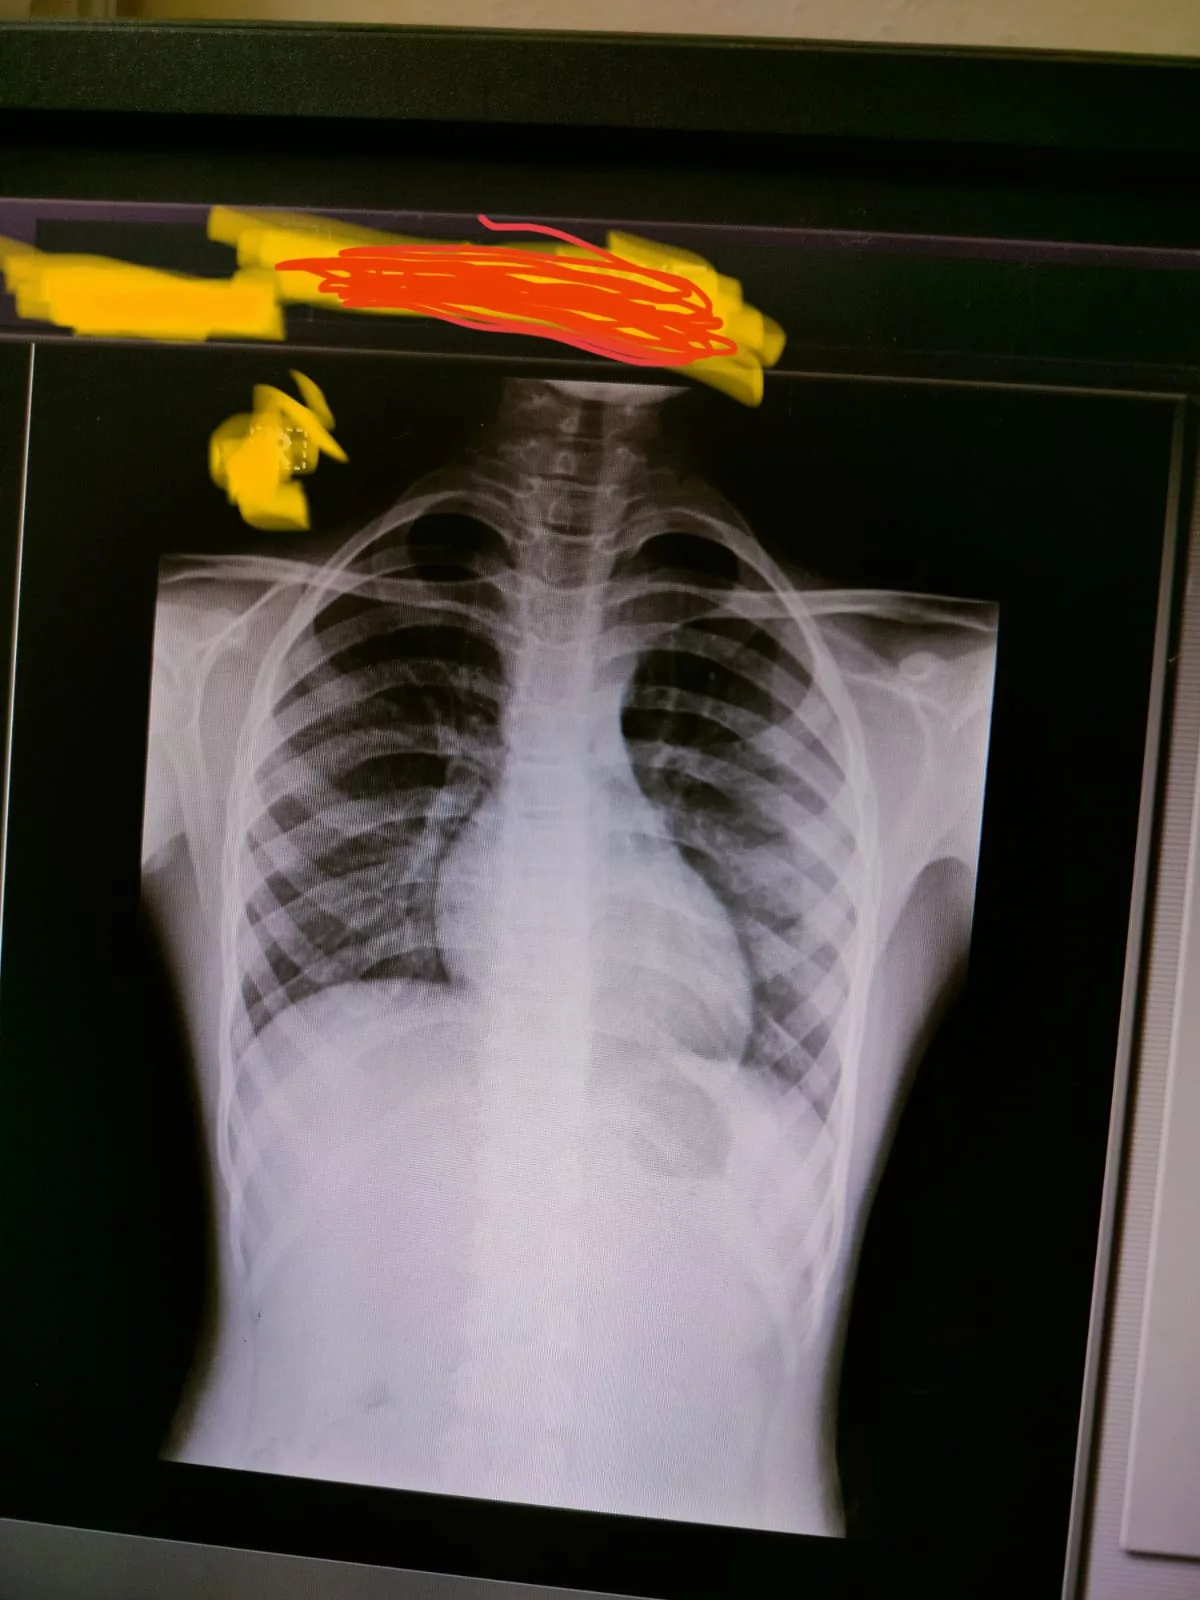

प्रतिदिन हज़ारों मरीजों का इलाज करने वाला हमीदिया हॉस्पिटल का एक्स-रे विभाग कई महीनों से बीमार चल रहा है लेकिन जि़म्मेदार अधिकारी इस ओर ध्यान नहीं दे रहे हैं। बताया जा रहा है कि कई महीनों से एक्स-रे फिल्म उपलब्ध नहीं है। मरीज का एक्स-रे करने के बाद टेक्निशियन द्वारा कंप्यूटर की स्क्रीन से मोबाइल से फोटो खींचकर दी जाती है। जिसे देखकर डाक्टर उपचार लिख रहे हैं।

ऐसे में जिन के पास एंड्राएड फोन है उनका तो काम हो जाता है। लेकिन जिस के पास नहीं है उन्हें काफी परेशानियों का सामना करना पड़ता है। हॉस्पिटल में फिल्म कब तक उपलध होगी इस की जानकारी किसी को भी नहीं है।